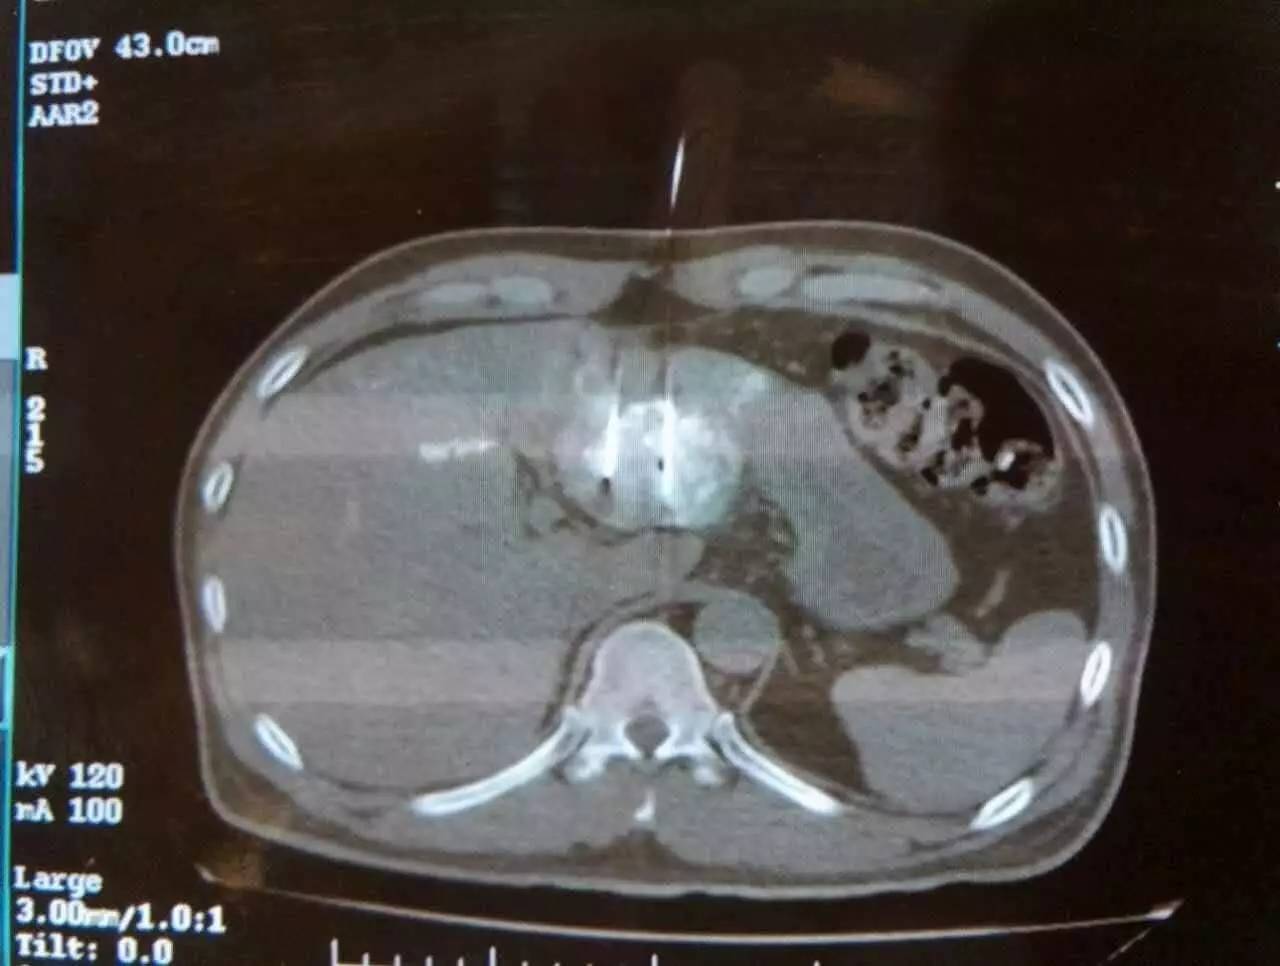

手术患者潘先生今年51岁,来自越南,今年7月在当地一次CT检查中发现肝左叶有一个4×4.3cm大小肿瘤,查血结果显示AFP665ng/ml。当地医生建议手术切除,潘先生拒绝了,随后在家自服中药。2016年11月11日,潘先生返院复查,CT和抽血结果分别显示:肝左叶肿瘤较前增大,AFP 1225ng/ml。病情有所恶化。

2016年11月19日,潘先生来到广州现代医院,经细致检查,被确诊为原发性肝中分化肝表皮细胞癌Ⅱ期。此时,患者的肝左叶肿瘤已增至5cm,AFP达900ng/ml。